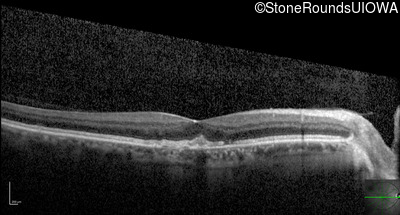

Optical Coherence Tomography - Right - 20/20

Exemplar / OCT Stack